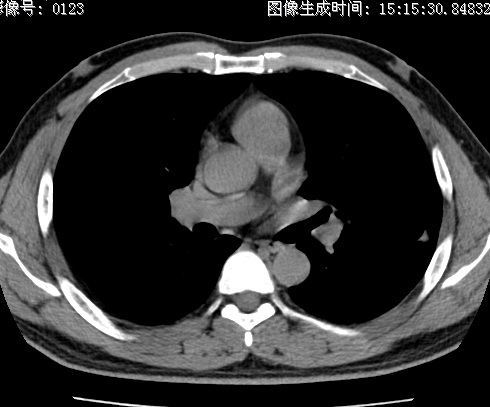

以下是引用zhao_bin2008在2010-1-4 20:15:00的发言:[br]先天性肺囊肿或小的肺隔离症?

以下是引用卜一在2010-1-4 22:09:00的发言:[br]先天性肺囊肿或小的肺隔离症?支持!

以下是引用zsl6918在2010-1-5 5:23:00的发言:[br]良性改变!肺囊肿,先天性支气管闭锁,血管畸形等均有可能。

以下是引用影像之路在2010-1-6 11:10:00的发言:[br]腺癌,最终的病检有些出乎意料之外,术前同志们大多考虑为肺囊肿或小的肺隔离征 [br]回过头来看 小结节呈分叶状,其内侧有一条较粗的静脉供血或许能成为支持诊断腺癌的理由